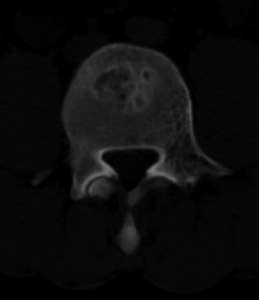

男,20,士兵,腰痛3年多,无外伤史

都是同一幅图啊,椎体内椎间盘突出。

支持!并多个椎体形成:“许莫氏”结节!

考虑:1、多发许莫尔氏结节形成;

2、建议平行腰5椎体扫描或冠矢状曲面重建除外椎弓峡部断裂。

倒数7~9幅图像示椎体后缘双边征及双关节征,支持l5轻度滑脱。

1、多发许莫尔氏结节形成;

2、椎弓峡部断裂。

3、l5轻度滑脱。

1、多发许莫氏结节。

2、腰5双侧椎弓峡部崩裂并i度前滑脱,楼主椎间盘扫描角度有问题,另外需要反倾角扫描腰5椎弓峡部。

2、腰5双侧椎弓峡部崩裂并i度前滑脱。